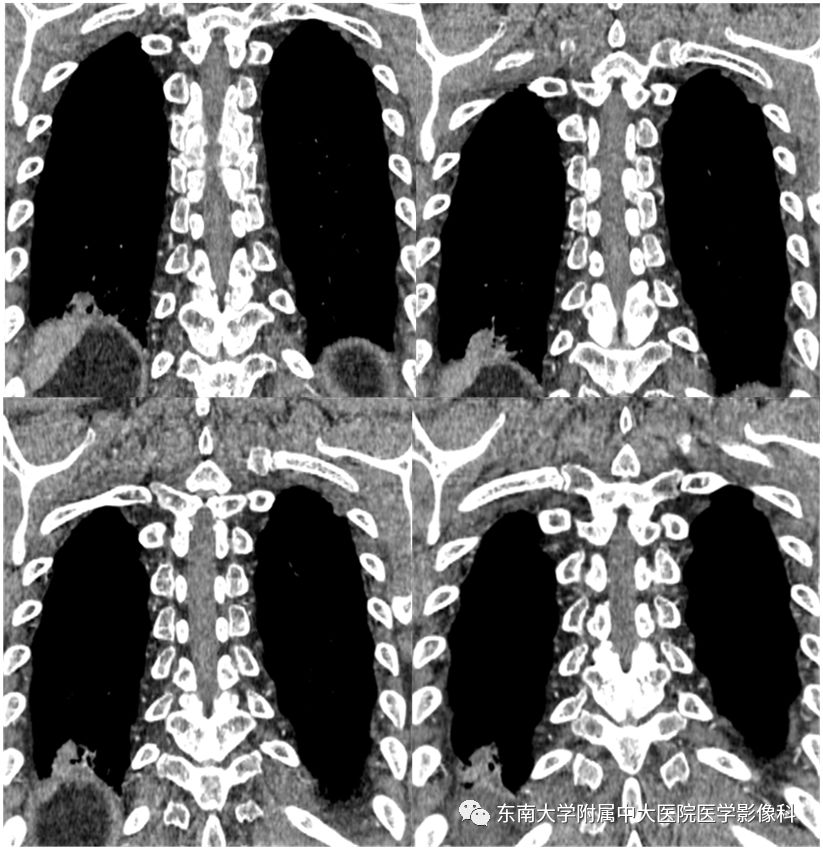

张力性纵隔气肿影像表现及严重度分级